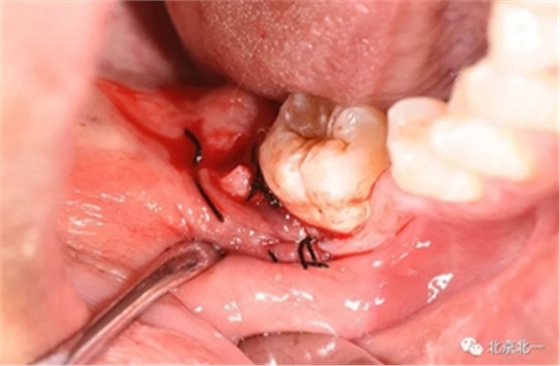

术后强调冲洗创口, 搔刮血液充盈。

缝合。